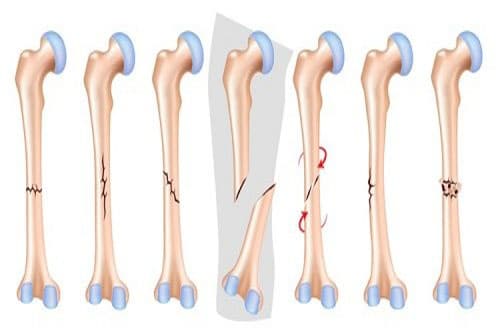

Gãy xương được phân thành 4 loại chính đó là: di lệch, không di lệch, hở và kín.

* Gãy di lệch: Là tình trạng xương tách ra thành hai hay nhiều phần và lệch làm cho hai đầu xương chỗ gãy không dính vào nhau

* Gãy xương không di lệch: Là tình trạng xương bị nứt một phần hoặc nứt hết theo chiều ngang, nhưng không chuyển và có thể duy trì liên kết giữa hai đầu xương gãy.

*Gãy xương kín: Là tình trạng xương gãy nhưng không có vết thủng hay vết thương hở ra trên da.

* Gãy xương hở: Là tình trạng xương bị gãy xuyên qua da, sau đó chỗ xương lồi có thể rút lại vào trong vết thương và không thể nhìn thấy qua da. Gãy xương hở có nguy cơ gây nhiễm trùng xương ở trong sâu.